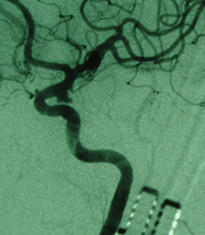

病例1:左侧前交通动脉瘤术后           病例1:左侧前交通动脉瘤术前

3例病人均为中年女性,均为突发头疼伴有意识障碍数小时入院,经CTA检查为宽颈动脉瘤,且瘤体不规则,介入栓塞技术要求较高,需术中支架辅助动脉瘤介入栓塞治疗。三例患者入院后,行积极术前准备。科室进行充分术前讨论。在吕正文主任指导下,由神经外科张明然、李庆民主治医师成功实施手术,手术过程顺利,术后病人恢复良好,无术中出血、血栓形成等并发症。